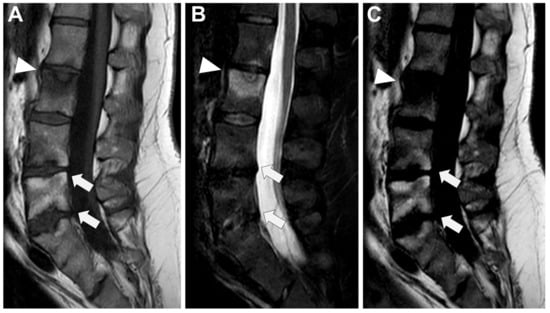

In Figure 7 an exemplificative case of PyS is presented.

Figure 7. A 73-year-old male presented with a rapidly evolving lumbar pain and fever, with an inflammatory syndrome on blood samples. A first MRI was performed as infectious spondylodiscitis was suspected, which included (A) STIR T2-weighted imaging (WI) and (B) fat sat T1-WI after gadolinium chelates injection. It shows a high signal intensity (SI) of the L3-L4 disc while other disks are in lower signal (black arrowhead), as well as linear subchondral contrast enhancement (CE) of the L3-L4 endplates both linear and more pronounced at the upper anterior corner of the L4 vertebral body (white arrowheads). Moreover, the left T11-T12 facet joints displayed marked edema of the subchondral bone and surrounding tissues (white arrows). A control MRI with SITR T2-WI (C) and fat-suppressed CE-T1-WI (D) was performed one month later, demonstrating a marked narrowing of the L3-L4 disk (black arrowhead), erosions of the vertebral body (dashed white arrows), extensive edema in the L3 and L4 vertebral body (white arrowhead), a persisting arthritis involving the left T1-T12 facet joint. Bacillus cereus was found on the Bacterial analysis of the L3-L4 disk biopsy.